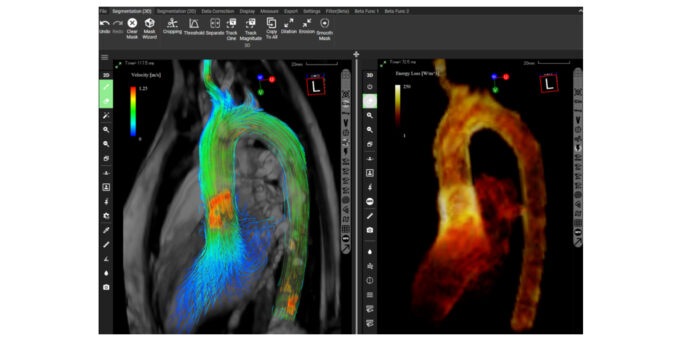

The US Food and Drug Administration (FDA) has approved the use of iTFlow in bloo...

Four-dimensional (4D) flow magnetic resonance imaging (MRI) has the potentia...